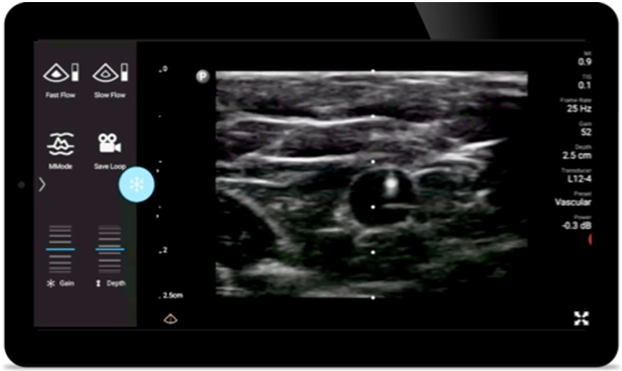

O ultrassom portátil Lumify para anestesiologia ajuda você a visualizar claramente a definição da borda na inserção da agulha, bem como nervos circundantes, vasos e planos fasciais.